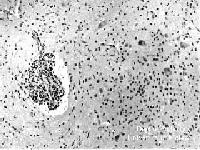

PATHOLOGIC STUDIES

OF ENTEROVIRUS 71 EPIDEMICS

PATHOLOGY OF FATAL

ENCEPHALOMYELITIS DURING AN

OUTBREAK OF ENTEROVIRUS 71

INFECTION IN CHINESE TAIPEI